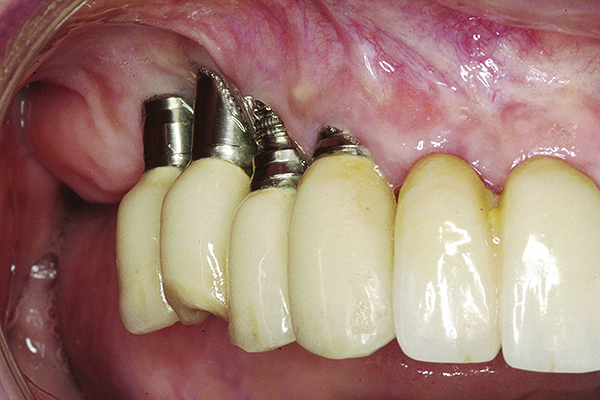

Fig 16 and Fig 17. Clinical photographs demonstrating bone loss and recession 20 years after prosthesis insertion. Initially the gingival margin covered the implant collars and threads. Fig 16: maxillary right; implants were placed at site Nos. 3 through 6. Fig 17: maxillary left; implants were placed at site Nos. 10 through 13.